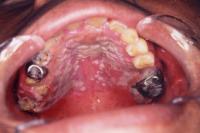

「口の中に白いものができた」という患者さんが多く来院されますが、その中でも注意が必要な疾患もありますので、一例をご紹介致します。

口腔カンジダ症

口腔カンジダ症とは、真菌(カビ)の一種であるカンジダ菌が顕著に増殖して、舌・頬粘膜などの口腔粘膜に痛みが生じる疾患です。義歯などを使用している方に多くみられます。綿棒などで擦過すると粘膜から容易に除去できる特徴があり、治療は抗カンジダ薬の内服や含嗽剤で行います。

口腔扁平苔癬

口腔扁平苔癬の原因は、肝機能障害などの全身的なものや、歯科用金属アレルギーや歯周病などの局所的なものまで多岐にわたります。病変の一部を採取する生検で診断を行うことができ、ステロイド製剤などを使用して数ヶ月単位で軽快すること多いです。

白板症

白板症とは、剥離できない白色の粘膜病変のことです。特に舌にできたものは、口腔癌に移行する可能性が高いため早期の診断と治療が必要となります。なかでも、びらん(赤くただれた状態)や2週以上治癒しない口内炎を伴う場合などは、「口腔潜在的悪性疾患」の可能背が高く、早期に生検を行って診断を急ぐことがあります。